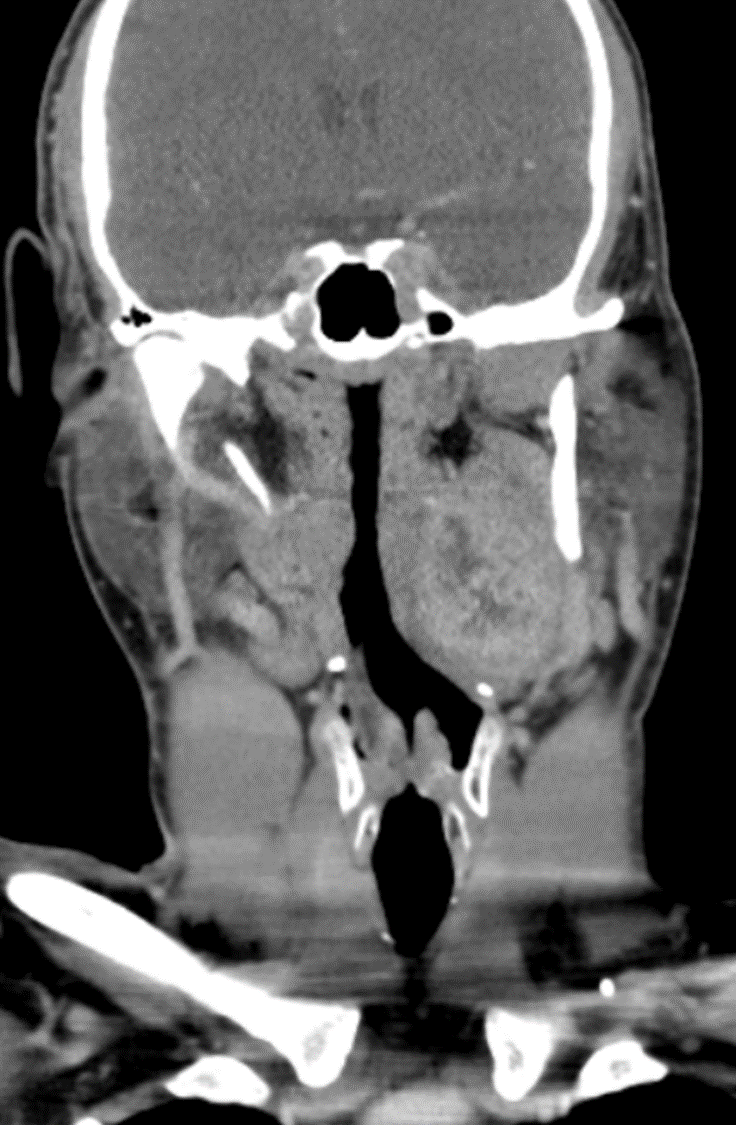

Clinical Pearl; Left Car...